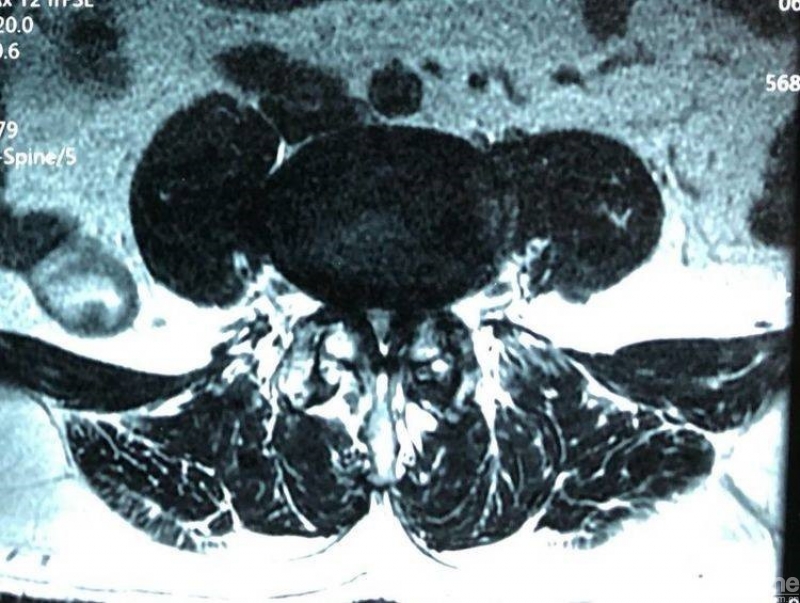

术前腰椎核磁共振横断面